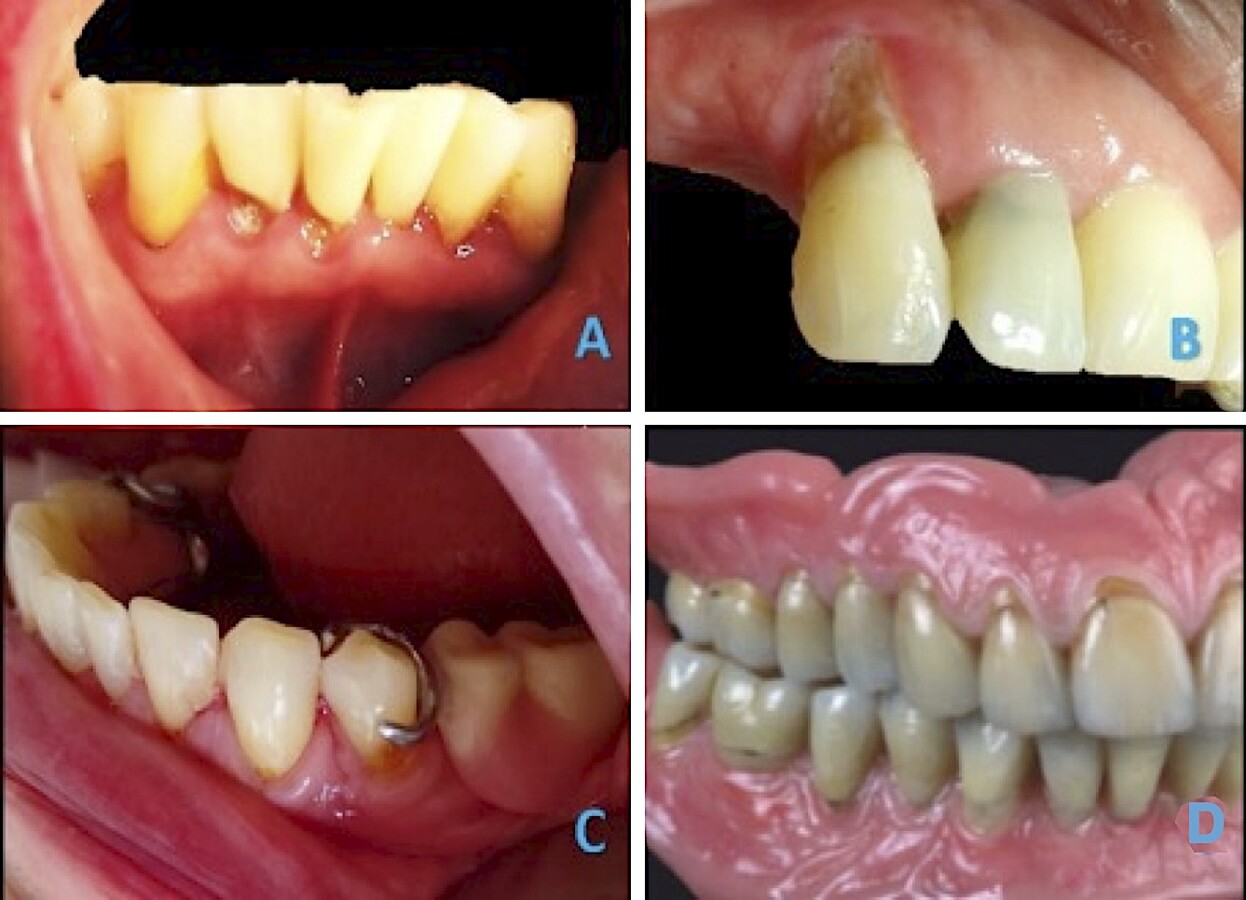

Figura 9 A) Paciente de 55 años con caries en tercio cervical de dientes anteriores en mandíbula B) Caries radicular promovida por soportación protésica. C) Recesiones y desajuste de retenedores de prótesis removible. D) Prostodoncia total con caracterización de LCNC.